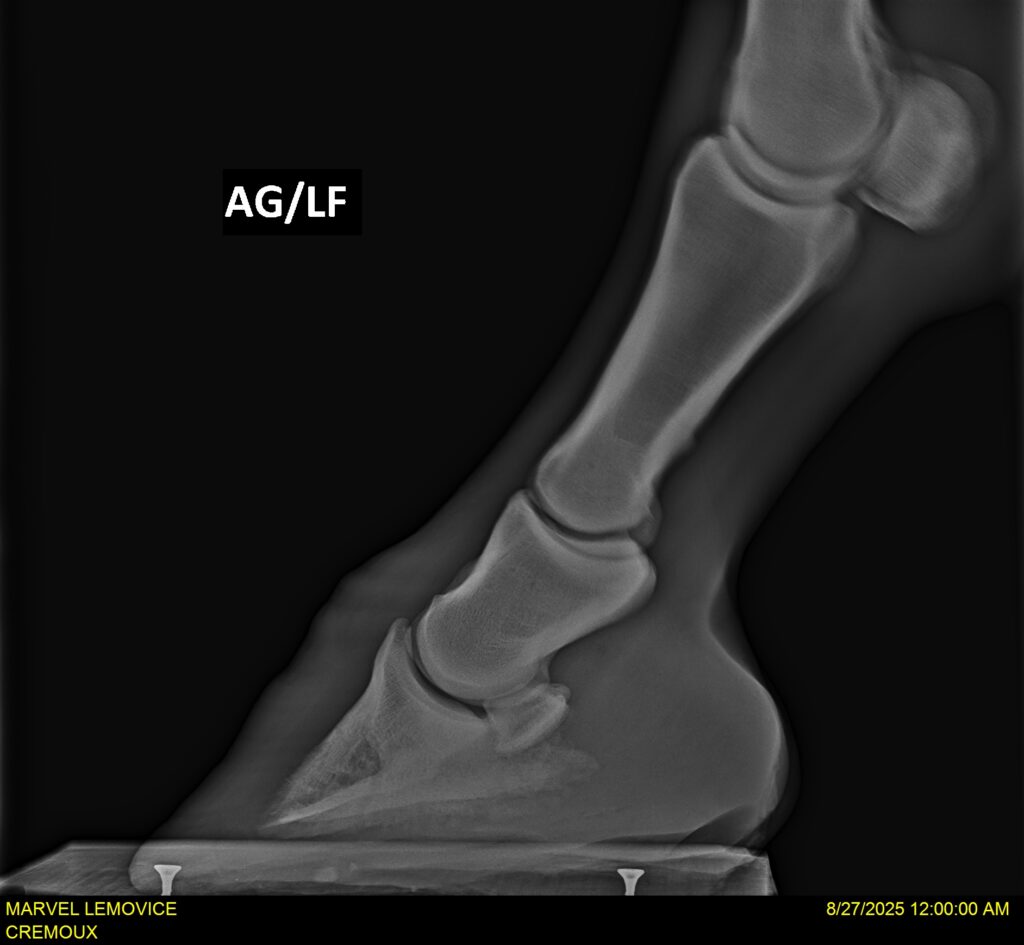

MARVEL LEMOVICE, hongre, Selle Français prend 4 ans en 2026. POPSTAR LOZONAIS x ROSIRE sur une excellente souche maternelle de l’élevage PLATIERE. Débourré aux trois allures et mise en route à l’obstacle. Super modèle avec du cadre et de la force, cheval respectueux avec des moyens. Très agréable au quotidien. Transport OK, maréchalerie OK, santé RAS, Bilan 20 clichés radios + clinique OK.

RADIOS ET CLINIQUE